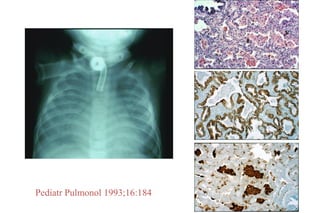

Pediatr Pulmonol 1993;16:184

UIP in Children

# Cases # UIP

ChILDRN1

378 0

Brompton2

203 1

Vanderbilt3

64 0

• True IPF/UIP probably does

not exist in children